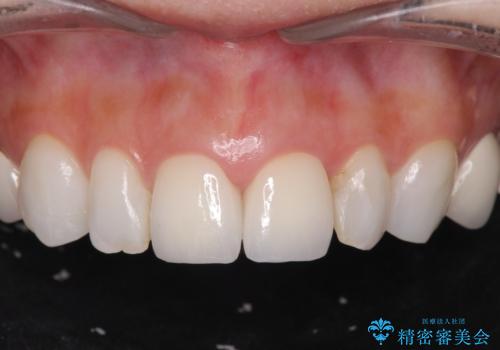

[前歯の歯根吸収] 前歯審美セラミックブリッジの製作

![[前歯の歯根吸収] 前歯審美セラミックブリッジの製作の治療後](https://seimitsushinbi.jp/wp/wp-content/uploads/2020/12/b6488efa9aee7b997214cf515ea1804a-500x350.jpg?v=1608091937)

![[前歯の歯根吸収] 前歯審美セラミックブリッジの製作の治療後](https://seimitsushinbi.jp/wp/wp-content/uploads/2020/12/737828edc16e3b9f995791946c6b661c-500x350.jpg?v=1608091941)

![[前歯の歯根吸収] 前歯審美セラミックブリッジの製作の治療後](https://seimitsushinbi.jp/wp/wp-content/uploads/2020/12/41e62ec4756c704eb3b8077ef9b2f37d-500x350.jpg?v=1608091945)

![[前歯の歯根吸収] 前歯審美セラミックブリッジの製作の治療後](https://seimitsushinbi.jp/wp/wp-content/uploads/2020/12/6ac036df0a2cbc9d87a792bd72a9d88a-500x350.jpg?v=1608091933)

![[前歯の歯根吸収] 前歯審美セラミックブリッジの製作の治療後](https://seimitsushinbi.jp/wp/wp-content/uploads/2020/12/19830355f5465c7a95254eba7dcdea19-500x350.jpg?v=1608091953)

![[前歯の歯根吸収] 前歯審美セラミックブリッジの製作の治療後](https://seimitsushinbi.jp/wp/wp-content/uploads/2020/12/3c40b5115b5a5781bfd498e7dabdb1f2-500x350.jpg?v=1608091949)

![[前歯の歯根吸収] 前歯審美セラミックブリッジの製作の治療後](https://seimitsushinbi.jp/wp/wp-content/uploads/2020/12/3215641ddc008e737ece410df3f195d0-500x350.jpg?v=1608091956)